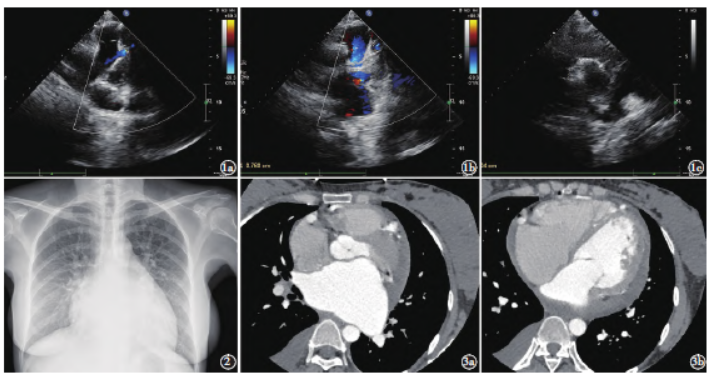

超声心动图

提示:肺动脉瓣上10 mm 处可见异常管状开口,开口内径7 mm,探及向肺动脉内连续异常分流,流速约103 cm/s;右冠状动脉开口位置正常,近段扩张,内径约10 mm,左冠状动脉开口未探及;二尖瓣及三尖瓣中度关闭不全;左心扩大;心包少量积液;肺动脉高压

(图1)。

胸部正位片示:心影增大,肺门部血管充血改变(图2)。冠状动脉CT 血管造影

图1 a)、b)超声心动图肺动脉长轴切面显示肺动脉瓣上10 mm 处见内径约7 mm 的异常管状开口。彩色多普勒示向肺内的连续分流信号;c)超声心动图主动脉根部短轴切面示右冠状动脉增粗,内径约10 mm。图2 胸部正位片示心影增大,双侧肺门充血改变。图3a)、b)轴位冠状动脉CTA示心腔增大。